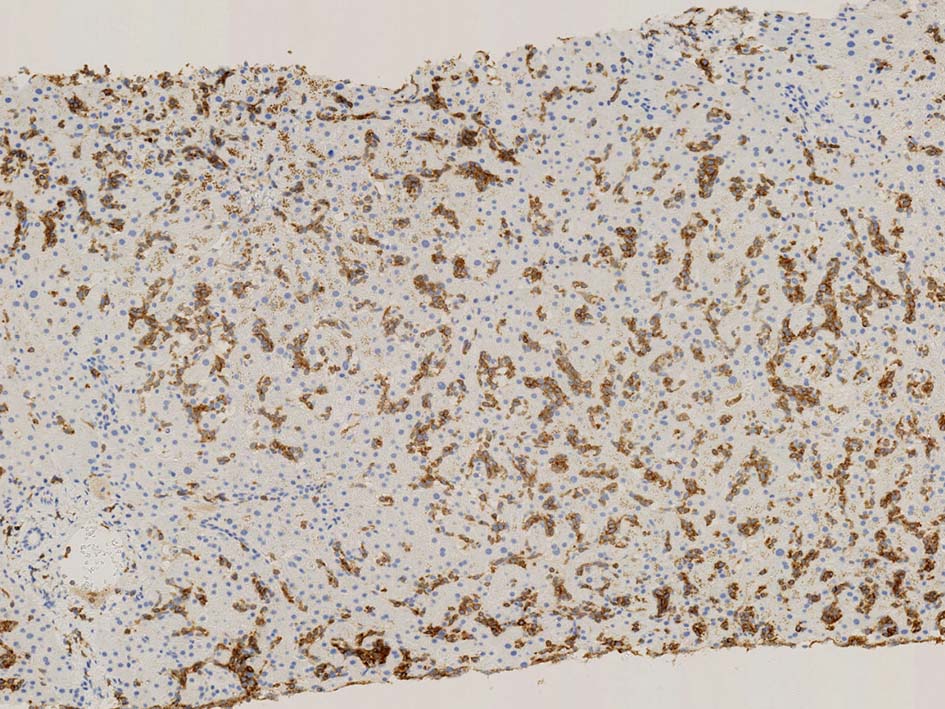

肝針生検組織; 類洞に細胞浸潤が認められ, 非浸潤部との境界がぼんやりと認められる. 類洞と異なり, グリソン鞘は腫瘍細胞の浸潤が乏しいか, ほとんど認められない.

類洞内に浸潤増殖するリンパ腫細胞: 類円形・長円, 瓜状の核をもつ,細胞質の乏しい細胞(サムネイル画像のクリックで大きな画像が見られます)

類洞内で増殖する腫瘍細胞はCD3+, CD7+のT-cellであるがCD5発現が弱く, 異常なT-cellである.

CD4は類洞内皮/macrophageの一部が陽性であるが, 類洞内腫瘍細胞の多くは陰性を示す(陽性と間違えないこと). CD8陰性. CD20陽性リンパ球はごく少ない.

TIA1は陽性であるが, granzymeBは陰性細胞が多い.